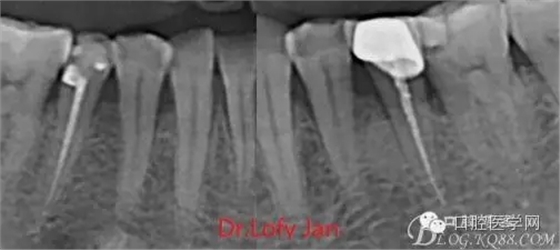

X線技術(shù)在根管治療中的重要性主要體現(xiàn)在以下幾個方面:

①有助于發(fā)現(xiàn)牙體和根尖周組織的異常改變,如牙折、牙內(nèi)吸收、髓腔鈣化及根尖囊腫;

②有助于確定牙根和根管的數(shù)目、位置、形態(tài)、方向和彎曲情況;

③有助于了解以前曾作過的治療情況,為再治療提供依據(jù);

④在操作前估計根管的工作長度;

⑤評價根管充填的質(zhì)量以及療效。